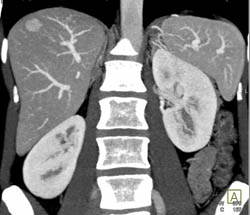

Focal Nodular Hyperplasia (FNH)